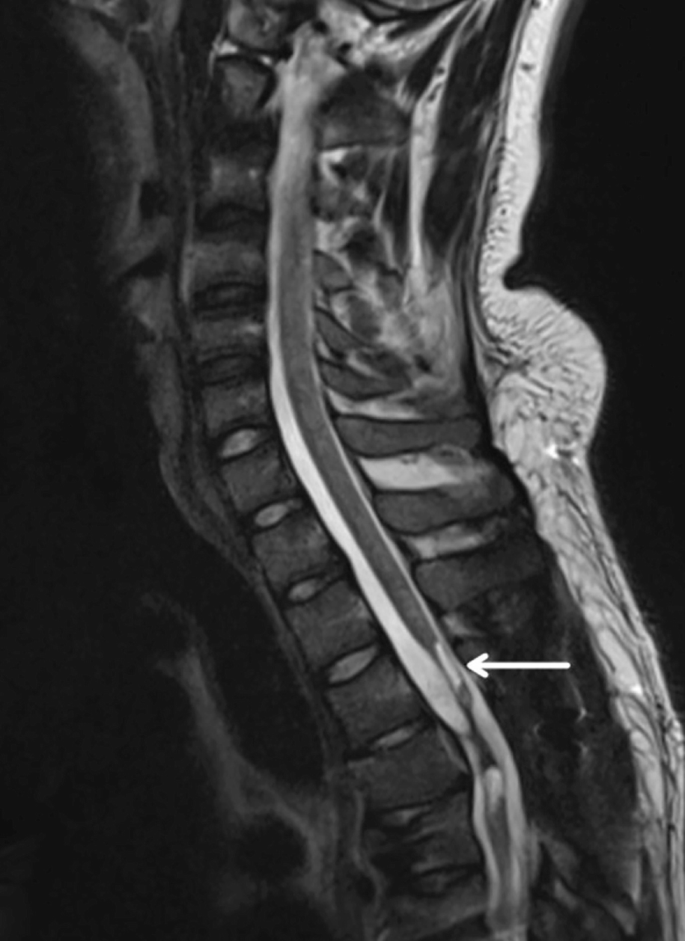

創(chuàng )傷性脊髓損傷是由于脊柱受到突然的強力撞擊,導致椎骨骨折、脫臼、擠壓或壓縮(圖1)。主要原因包括機動(dòng)車(chē)事故,其中汽車(chē)和摩托車(chē)碰撞占每年新增脊髓損傷病例的近一半。跌倒,尤其是65歲及以上人群的跌倒,是造成脊髓損傷的重要原因,約占60%。體育活動(dòng),例如沖擊性運動(dòng)和淺水潛水,約占此類(lèi)損傷的10%。

圖1:X射線(xiàn)圖像顯示脊髓損傷,椎骨骨折和移位,如白色箭頭所示